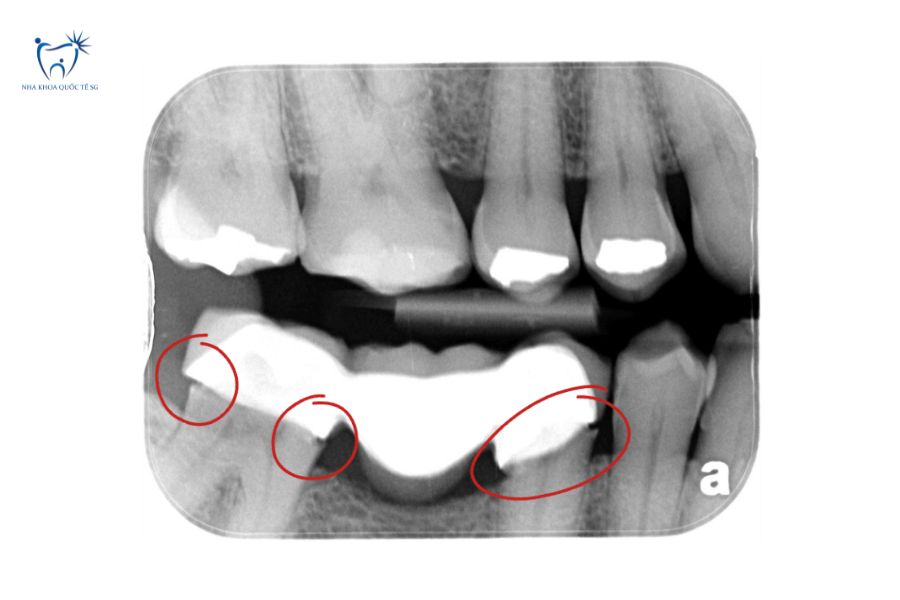

Ảnh chụp CT cầu răng sứ bị hở cần điều trị

Khắc phục cầu răng sứ bị hở bằng cách trám composite tạm thời cho trường hợp nhẹ, tháo và làm lại cầu sứ mới cho trường hợp nặng, hoặc cấy ghép Implant nếu răng trụ đã hỏng.

Khi phát hiện dấu hiệu cầu răng sứ bị hở, bạn cần đến nha khoa uy tín càng sớm càng tốt để được kiểm tra và xử lý kịp thời. Tại Nha Khoa Quốc Tế SG, bác sĩ sẽ thăm khám toàn diện, chụp X-quang kỹ thuật số để đánh giá chính xác tình trạng răng trụ và mức độ hở của cầu răng, từ đó đưa ra phương án điều trị phù hợp nhất.